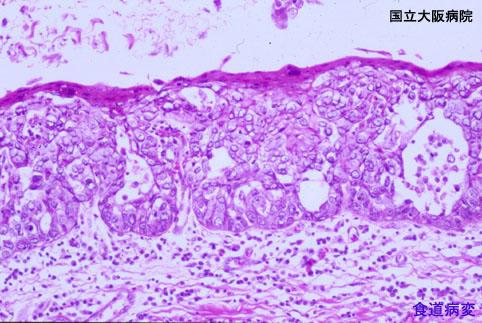

症例提示(所在地,施設名等): 大阪府・ 大阪医療センター

疾患(病理主体)の分類悪性上皮性腫瘍/類基底細胞癌

部位(臓器別)食道/下

検査方法ミクロ

腫瘍の肉眼分類0型(表在型)/その他

病変の最大径(ミリ)40以上

腫瘍の深達度mm

多発腫瘍(同一臓器)

多重腫瘍(他臓器)有(同時性)